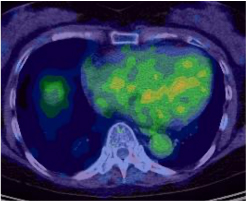

サルコイドーシスは、非乾酪性肉芽腫という病理変化を伴う炎症性疾患です。心臓以外にも眼、皮膚、肺やリンパ節に起こり得ます。心臓においては、心筋の収縮障害から進行すれば心拡大が起きます。不整脈を併発しやすいことも知られています。診断には心臓MRIや血液検査のほかに、心臓にブドウ糖が取り込まれているか調べる核医学検査であるFluorodeoxyglucose-Positron Emission Tomography(FDG-PET)が病勢の把握に有用です。

心サルコイドーシスの活動期

心サルコイドーシスの活動期

ステロイド治療により

ステロイド治療により炎症・免疫反応が軽減